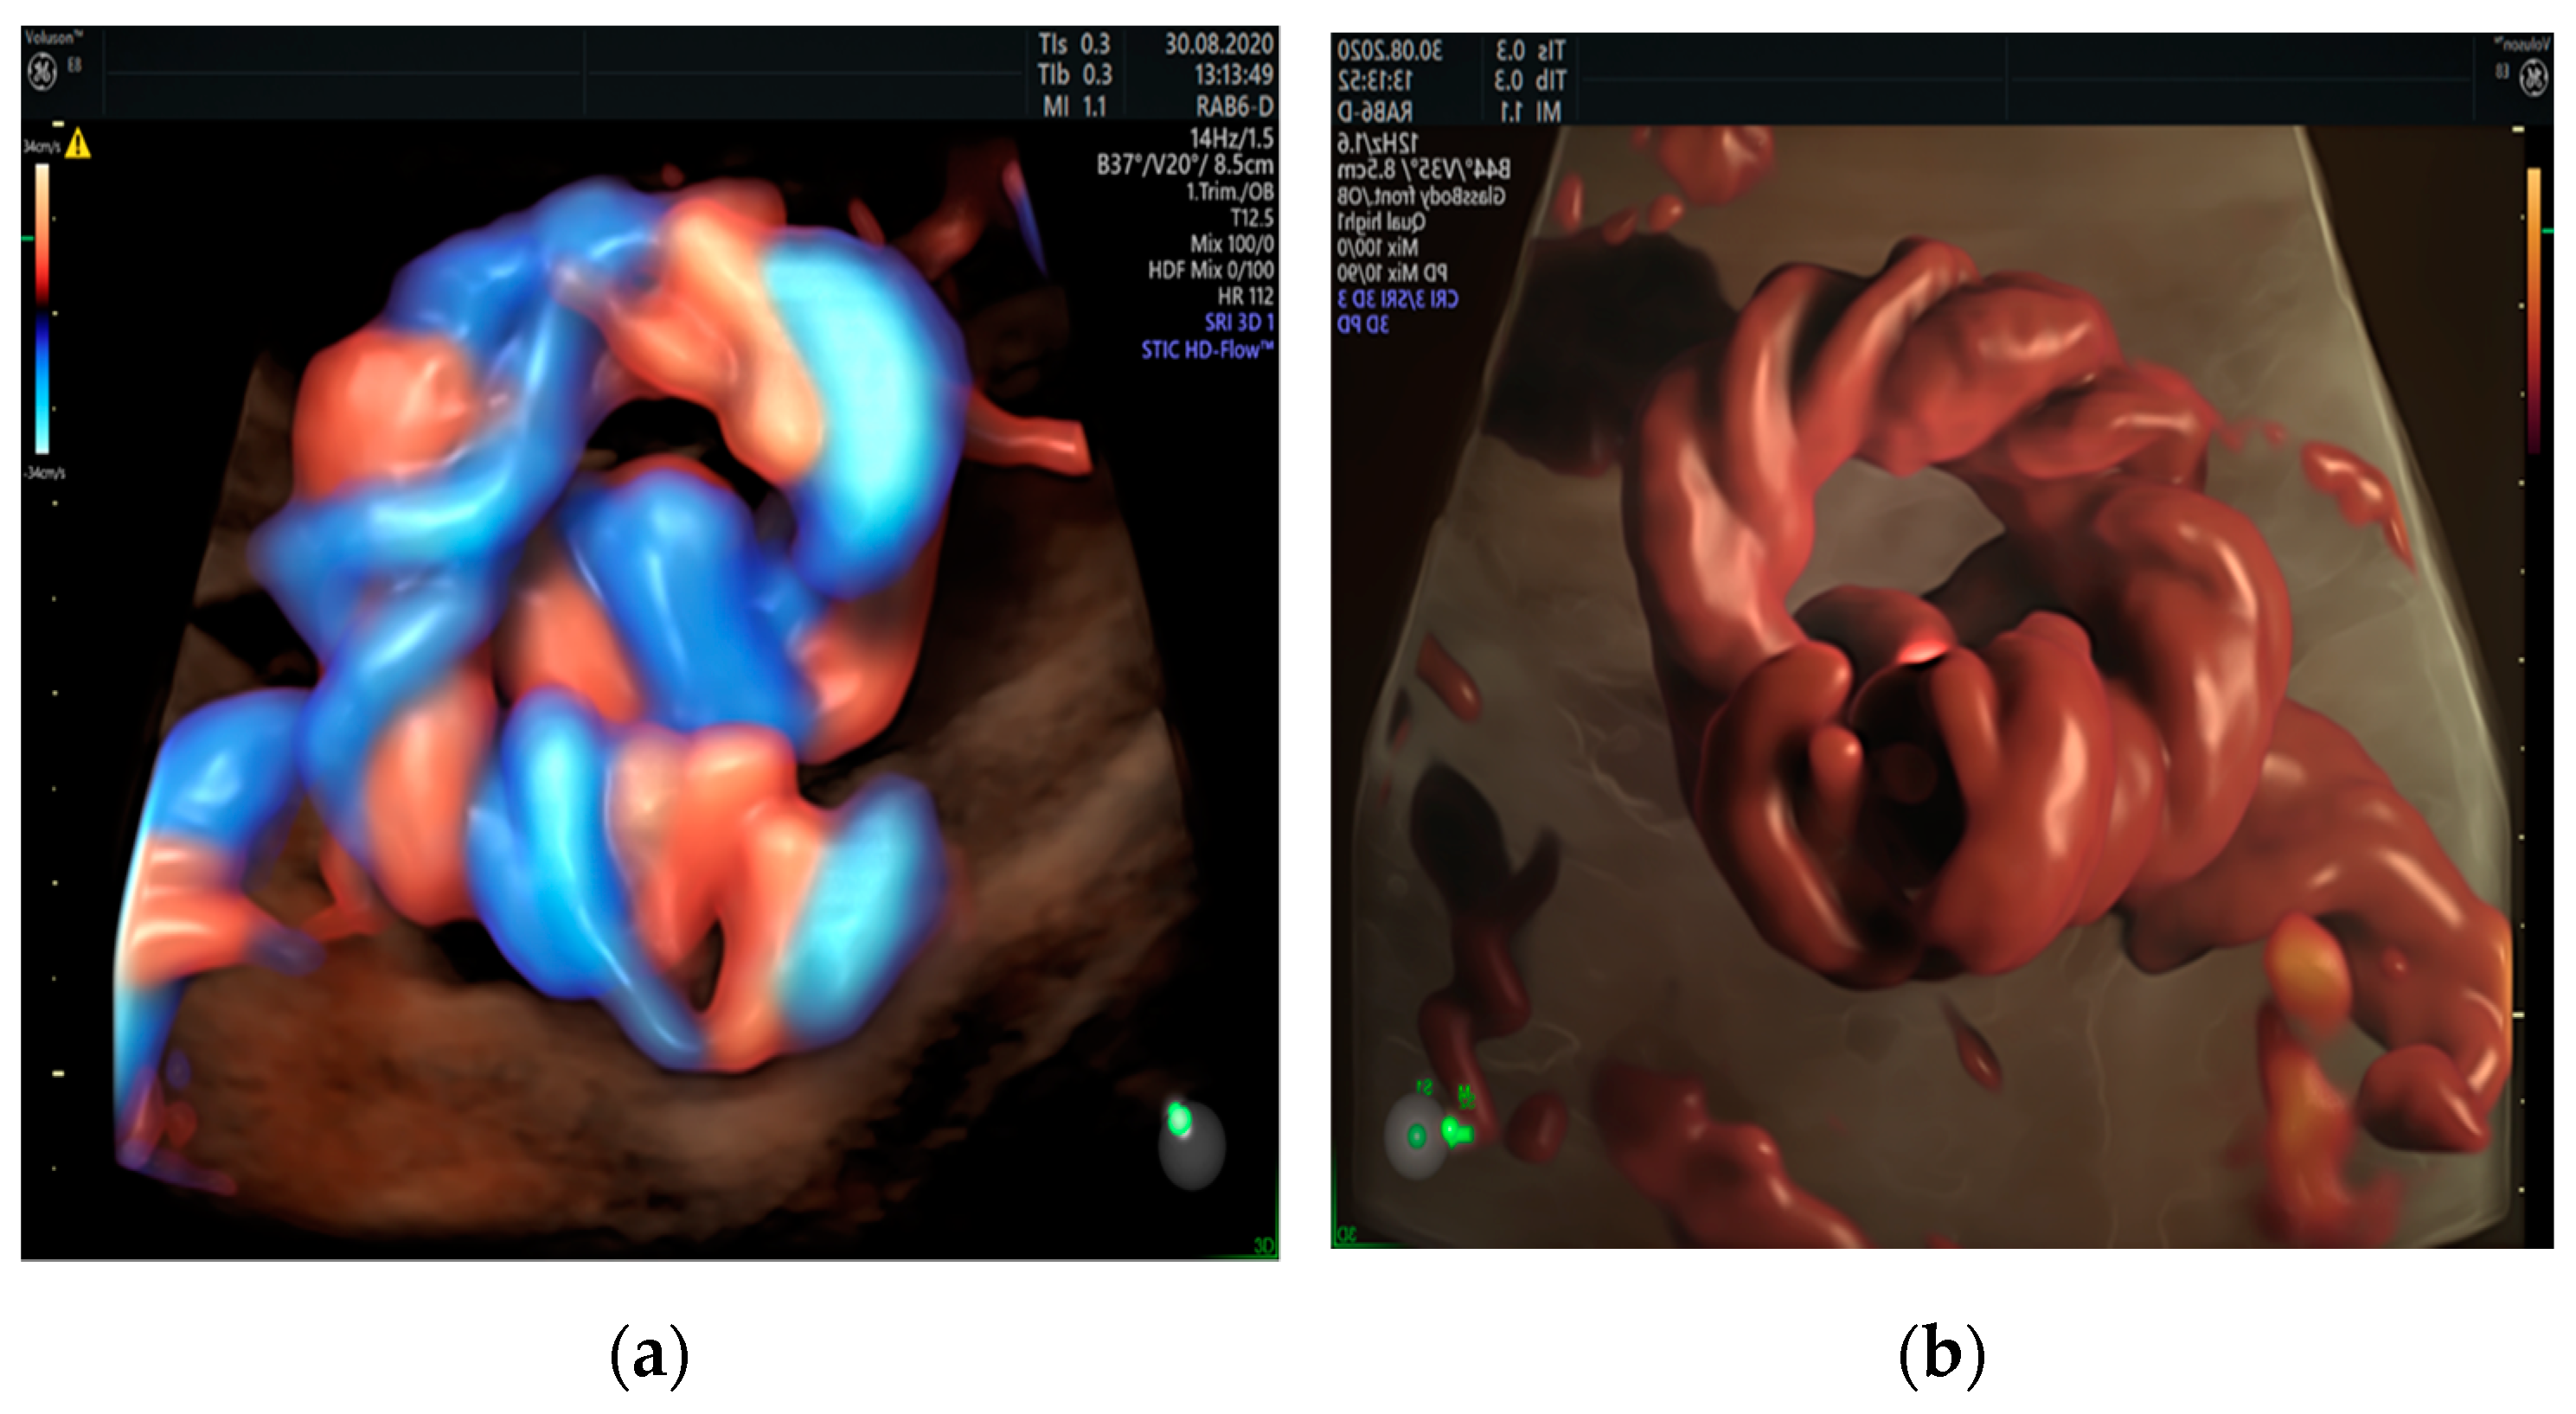

3.2. True Umbilical Cord Knot